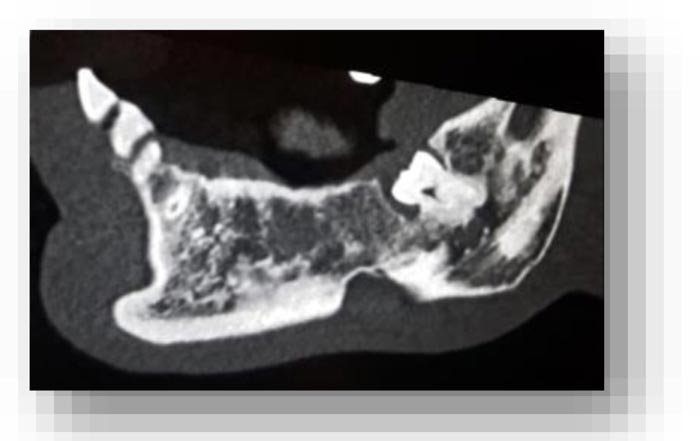

From the objective exam and the panoramic radiography, we observed the presence of multiple edentulous areas which needed to be rehabilitated. As part of an implant-prosthetic plan of care, Spiral Computerized Tomography was prescribed to him (Fig. 3), obtaining bi-dimensional reconstructions as panorex, parasagittal slices by multiplanar reformation and tridimensional reconstructions by volume rendering [12, 13].

In this radiographic exam, we found an oval notch with radiolucent, clear and regular borders, located in the inferior portion of the horizontal branch of the mandible, on the lingual side, near the angle of the mandible, and below the mandibular canal. The X-ray allowed precise measurement showing a height ranging between 13.5 mm and 17 mm and breadth between 6 and 8 mm (Figs. 4-5).

The bi-dimensional reconstructions in parasagittal slices also permitted better identification of the closeness of the bone cavity to the canal of the alveolar inferior omolateral nerve, whereas the computerized volume rendering offered a more accurate view of the surrounding anatomical features (Figs. 6-12).